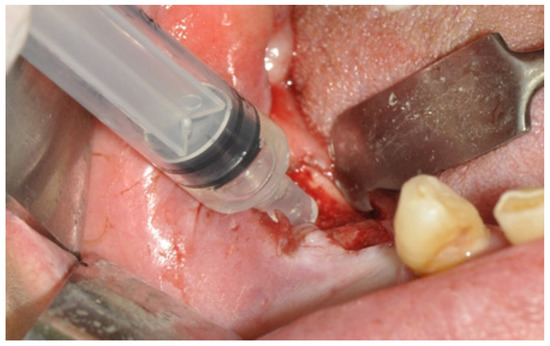

| Patient | Age | MRONJ Stage |

|---|---|---|

| Patient 1 | 44 | I |

| Patient 2 | 79 | II |

| Patient 3 | 61 | II |

| Patient 4 | 69 | I |

| Patient 5 | 85 | III |

| Patient 6 | 77 | I |

| Patient 7 | 65 | I |